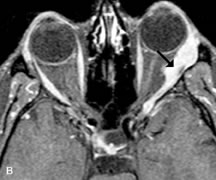

Pleomorphic adenomas demonstrate long T1 and T2 signal characteristics. They may show heterogeneity on T2-weighted images74 and moderate to marked enhancement with contrast.75 Signal characteristics of adenoid cystic carcinoma include hypointensity to fat on T1-weighted images, hyperintensity to fat with increased T2 weighting, and isointensity to fat on proton density-weighted studies (Fig. 23).31,75 Secondary bony alterations of the lacrimal fossa associated with lacrimal gland tumors, such as remodeling (benign mixed tumor) or destruction (adenoid cystic carcinoma), are seen indirectly on MR images; however, bone windows on CT scans provide better delineation of these changes. In contrast to the round or globular appearance of benign or malignant epithelial tumors of the lacrimal gland, lymphoproliferative tumors usually appear to be molding or draping onto the globe and the surrounding bony orbit.

Fig. 23. A. T2-weighted and (B and C) postcontrast fat-suppressed T1-weighted MR scans demonstrate an infiltrative lacrimal region mass than invades the lateral rectus muscle (arrows). This highly cellular lesion is seen to have a very hypointense appearance on the T2-weighted scan.